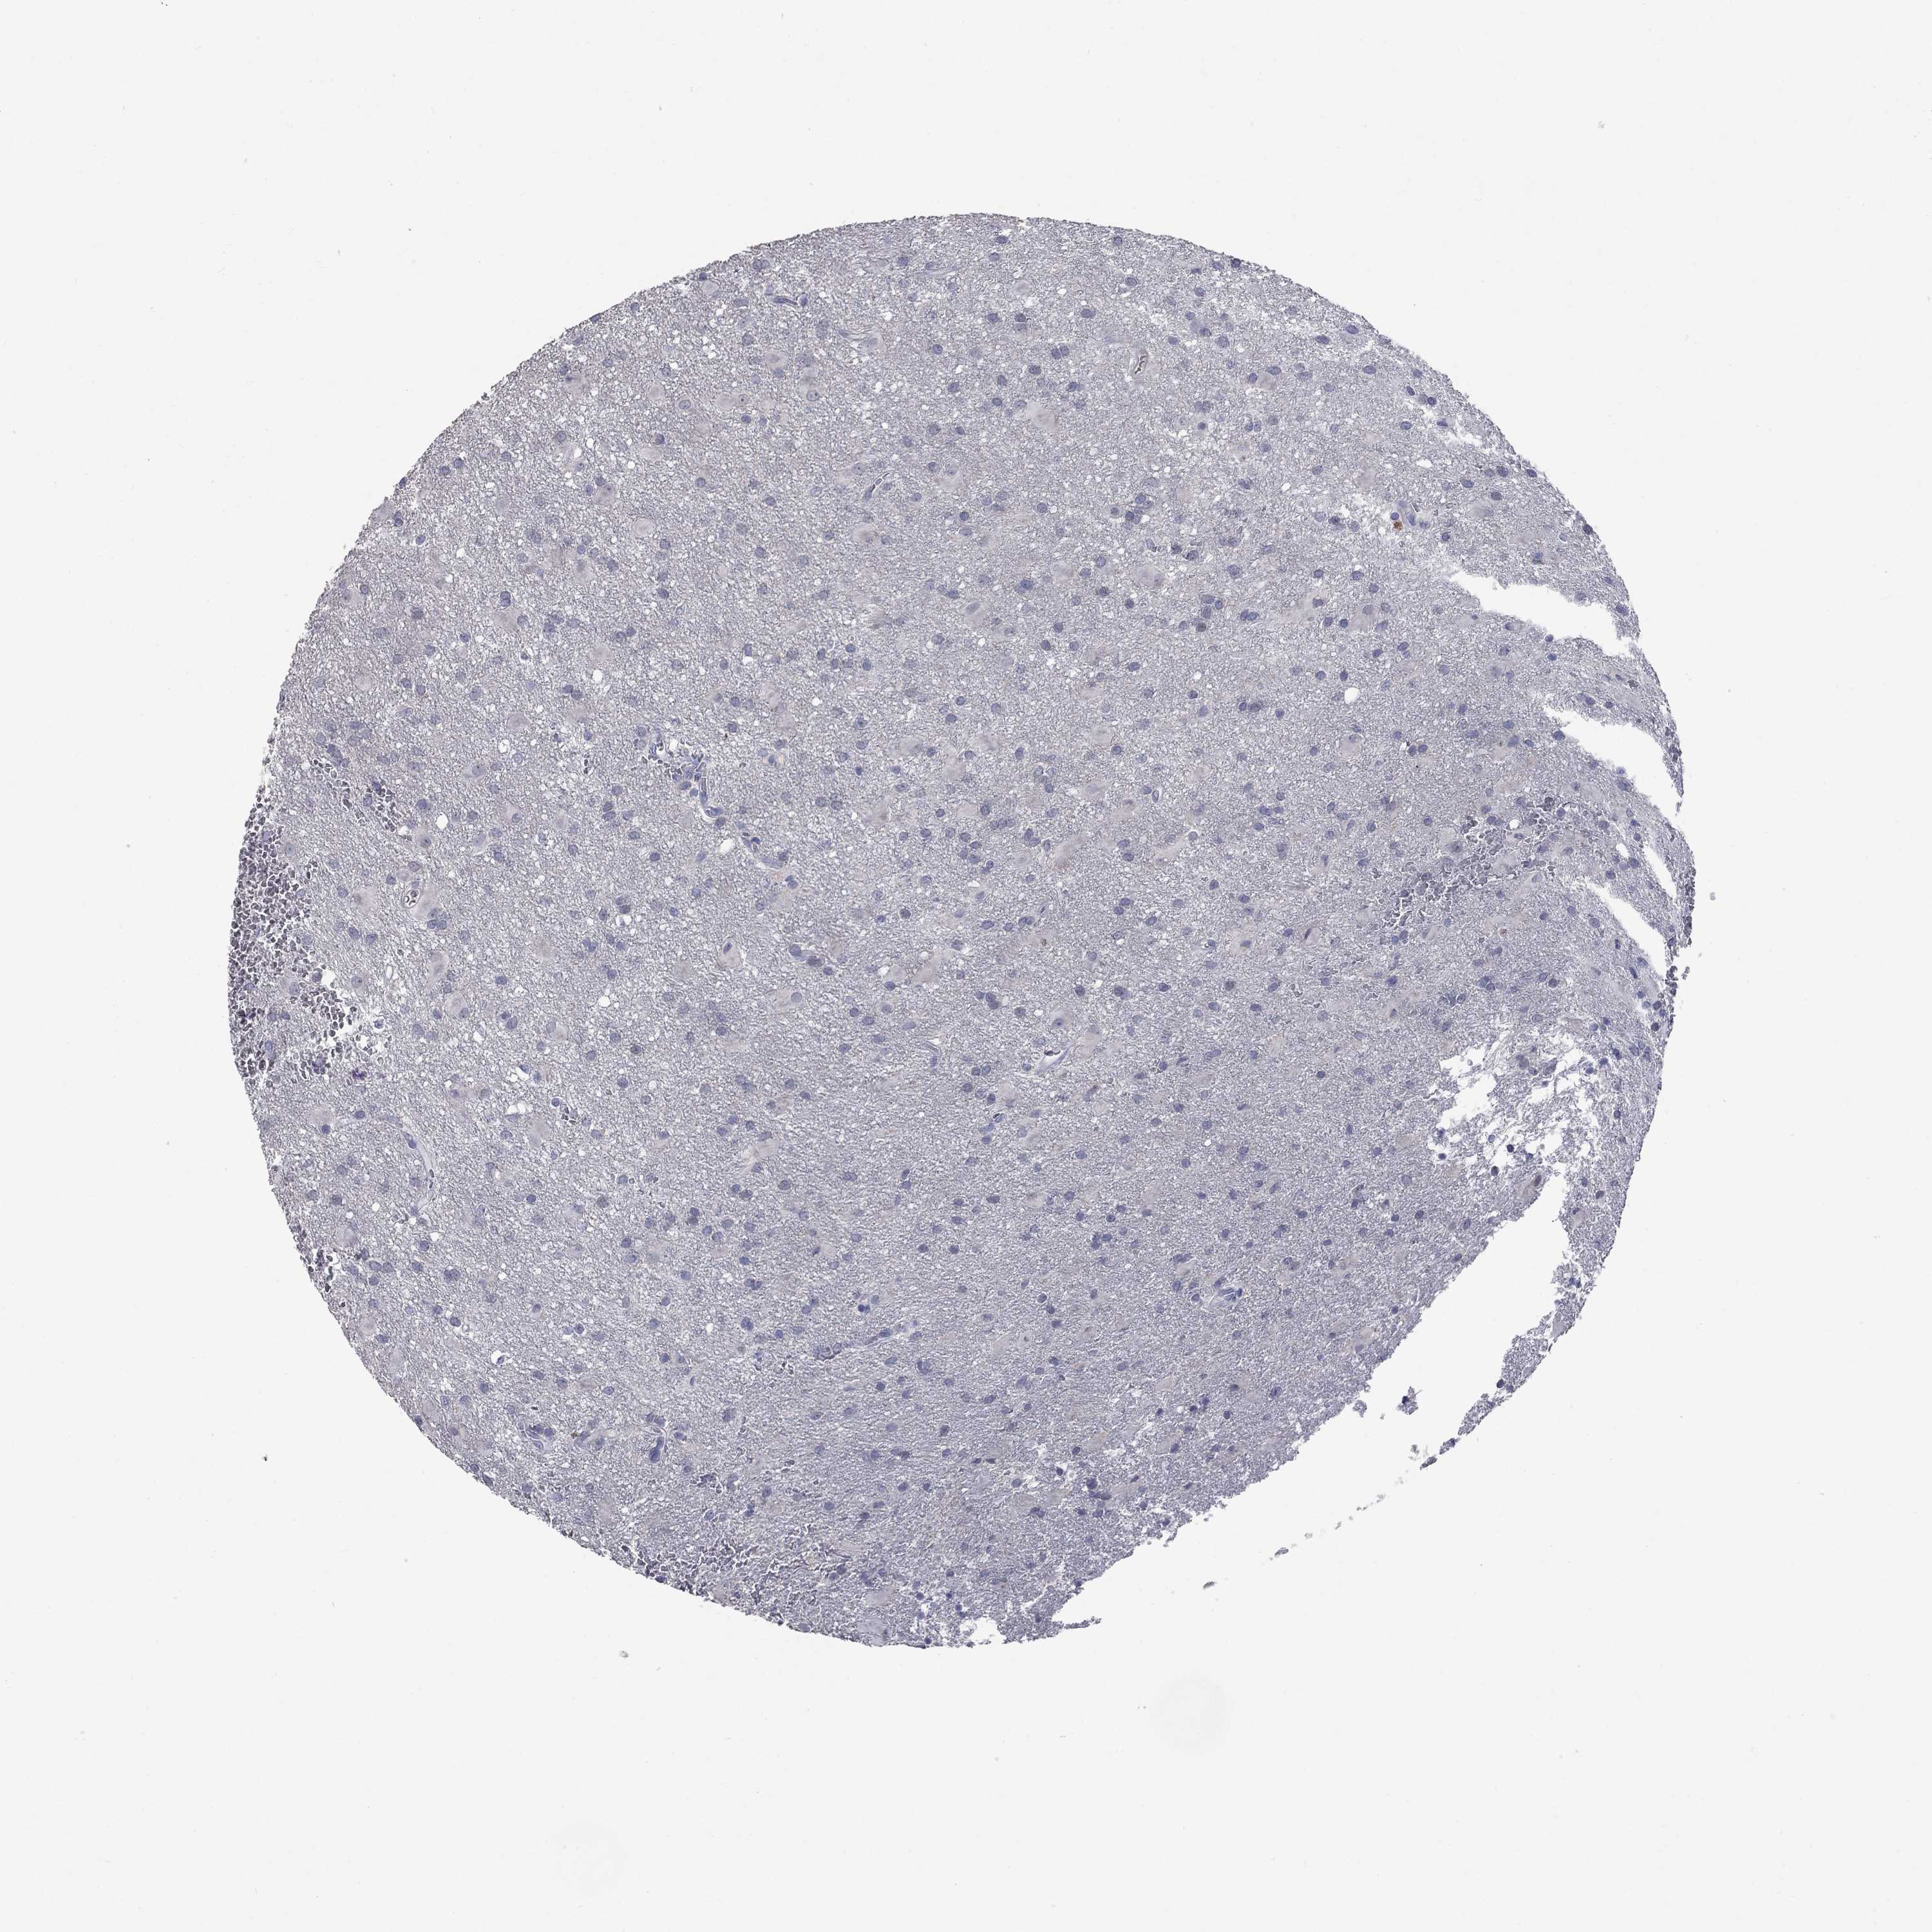

GLIOMA - Protein expressioni

A mouse-over function shows sample information and annotation data. Click on an image to view it in a full screen mode. Samples can be filtered based on level of antibody staining by selecting one or several of the following categories: high, medium, low and not detected. The assay and annotation is described here.

Note that samples used for immunohistochemistry by the Human Protein Atlas do not correspond to samples in the TCGA dataset.

Antibody stainingi

Antibody staining in the annotated cell types in the current human tissue is reported as not detected, low, medium, or high, based on conventional immunohistochemistry profiling in selected tissues. This score is based on the combination of the staining intensity and fraction of stained cells.

Each image is clickable and will lead to virtual microscopy that enables deeper exploration of all samples and also displays staining intensity scores, fraction scores and subcellular localization as well as patient and tissue information for each sample.

Antibody HPA068138

Antibody HPA071902

Glioma, malignant, Low grade

Glioma, malignant, High grade

Glioma, malignant, NOS